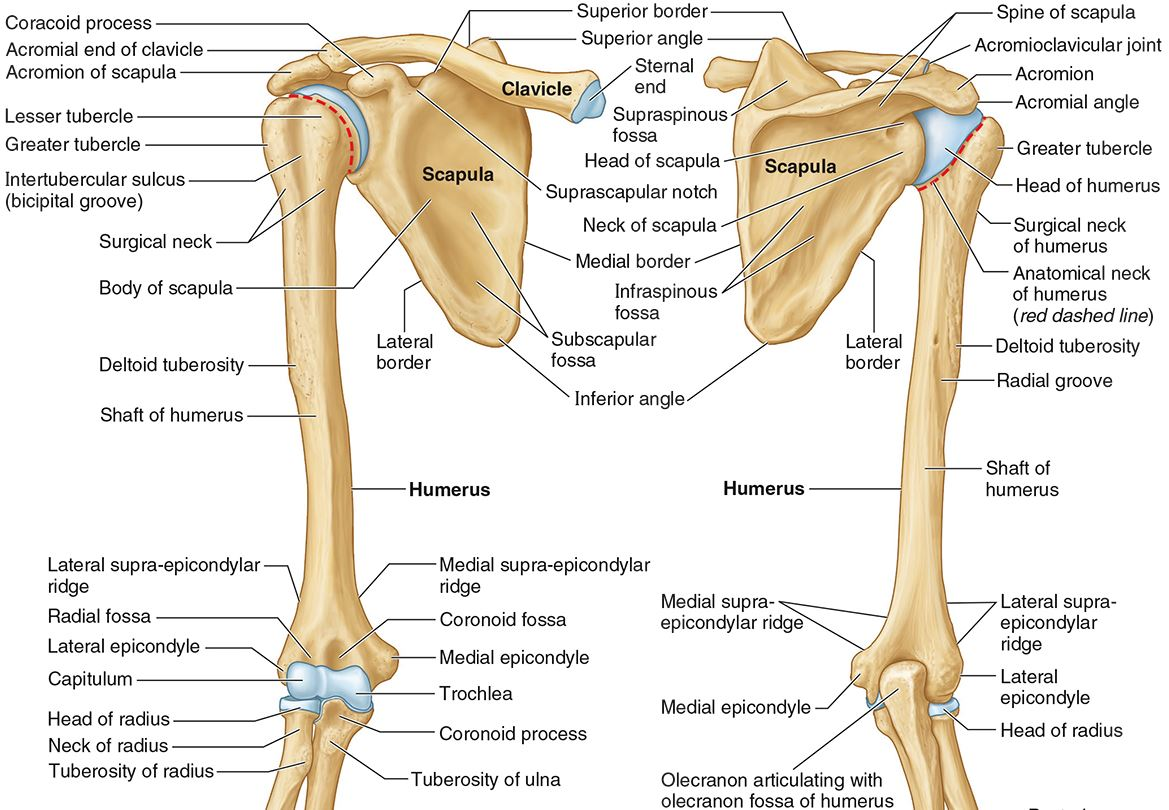

What part of the humerus is this?

The head of the humerus articulates with the scapula at the glenohumeral joint.

What part of the humerus is this?

The anatomic neck is an indentation distal to the head and provides an attachment for the fibrous joint capsule of the glenohumeral joint.

What part of the humerus is this?

The greater tubercle lies lateral and distal to the anatomic neck.

What part of the humerus is this?

The lesser tubercle lies on the anterior/medial side of the humerus, just distal the anatomic neck.

What part of the humerus is this?

The intertubercular (bicipital) groove lies between the greater and lesser tubercles.

What part of the humerus is this?

The surgical neck is a narrow area distal to the tubercles. It is a common site for proximal humerus fractures.

What part of the humerus is this?

The humeral shaft features the deltoid tuberosity laterally for the distal insertion of the deltoid muscle.

What part of the humerus is this?

The radial groove is an oblique depression that contains the radial nerve and deep brachial artery.

Which parts of the humerus is this?

The medial and lateral epicondyles are distal prominences to which many forearm tendons attach, near the elbow joint.

Which parts of the humerus is this?

The medial and lateral supracondylar ridges extend superiorly from the medial and lateral epicondyles.

Which parts of the humerus is this?

The trochlea and the capitulum (the condyles) are the most distal surfaces of the humerus, where it articulates with the forearm bones at the elbow joint

What part of the humerus is this?

The olecranon fossa is a posterior depression above the trochlea that receives that olecranon process of the ulna

What part of the humerus is this?

The coronoid fossa is an anterior depression above the trochlea that receives that coronoid process of the ulna.